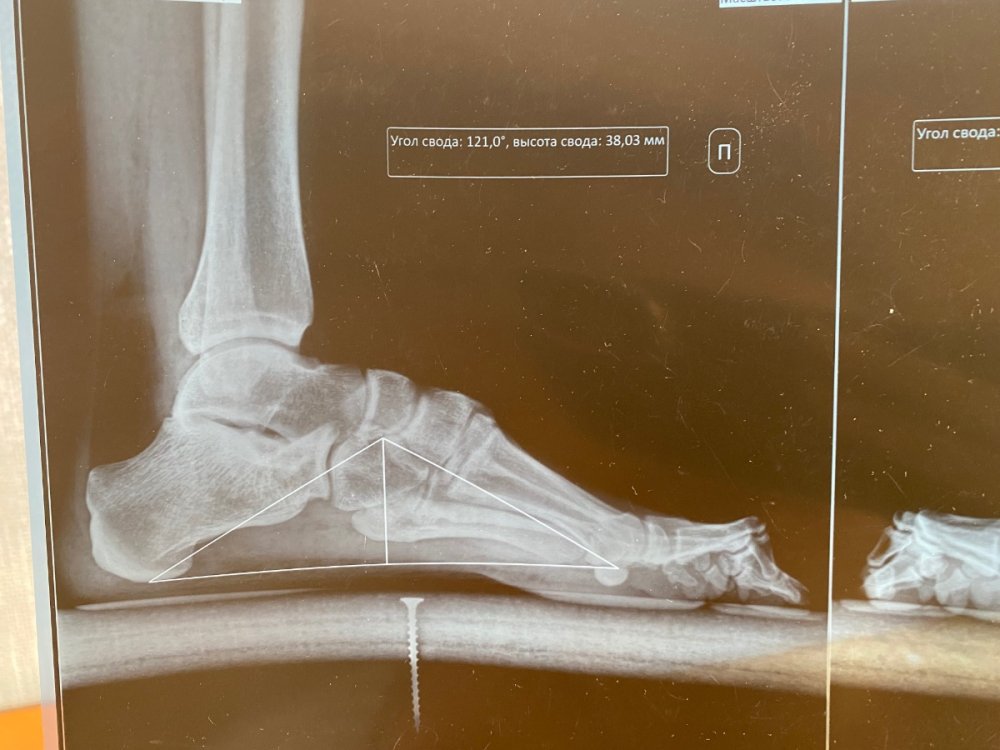

В военкомате направили в областную на подтверждение диагноза. Врач-ортопед выставил следующее заключение: «М20.1 Наружное искривление большого пальца (hallux valgus] (приобретенное)

Вальгусная деформация 1 пальца обеих стоп. Сгибательная контрактура пальцев обеих стоп.». На какую категорию годности я могу расчитывать?